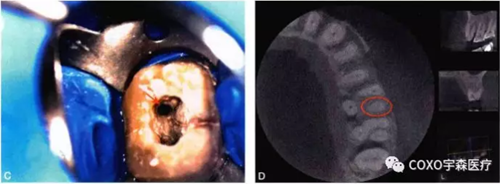

細(xì)小鈣化根管的根管口,即使是在口腔手術(shù)顯微鏡下,也不容易被發(fā)現(xiàn)。在鈣化根管的早期,鈣化牙本質(zhì)的顏色可能與周圍正常牙本質(zhì)不同,因此,多數(shù)情況下,利用口腔手術(shù)顯微鏡能夠發(fā)現(xiàn)根管所在位置。有的鈣化根管牙本質(zhì)與周圍牙本質(zhì)顏色相似,難以區(qū)分,此時借助手術(shù)顯微鏡的高倍放大作用,結(jié)合根管解剖知識,仔細(xì)觀察顏色的細(xì)微差異,有助于提高探查根管口的成功率。完全鈣化的根管,表現(xiàn)為均質(zhì)的硬組織結(jié)構(gòu),有時與正常牙本質(zhì)結(jié)構(gòu)難以區(qū)別,當(dāng)采用各種方法均無法疏通時,為了避免產(chǎn)生新的并發(fā)癥,不宜強行疏通,可定期追蹤觀察(圖4-2)